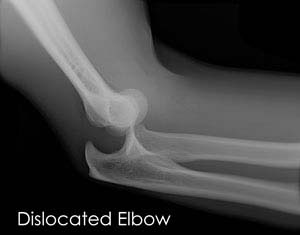

Know More - Elbow Dislocation

The arm in the human body is made up of three bones that join to form a hinge joint called the elbow.